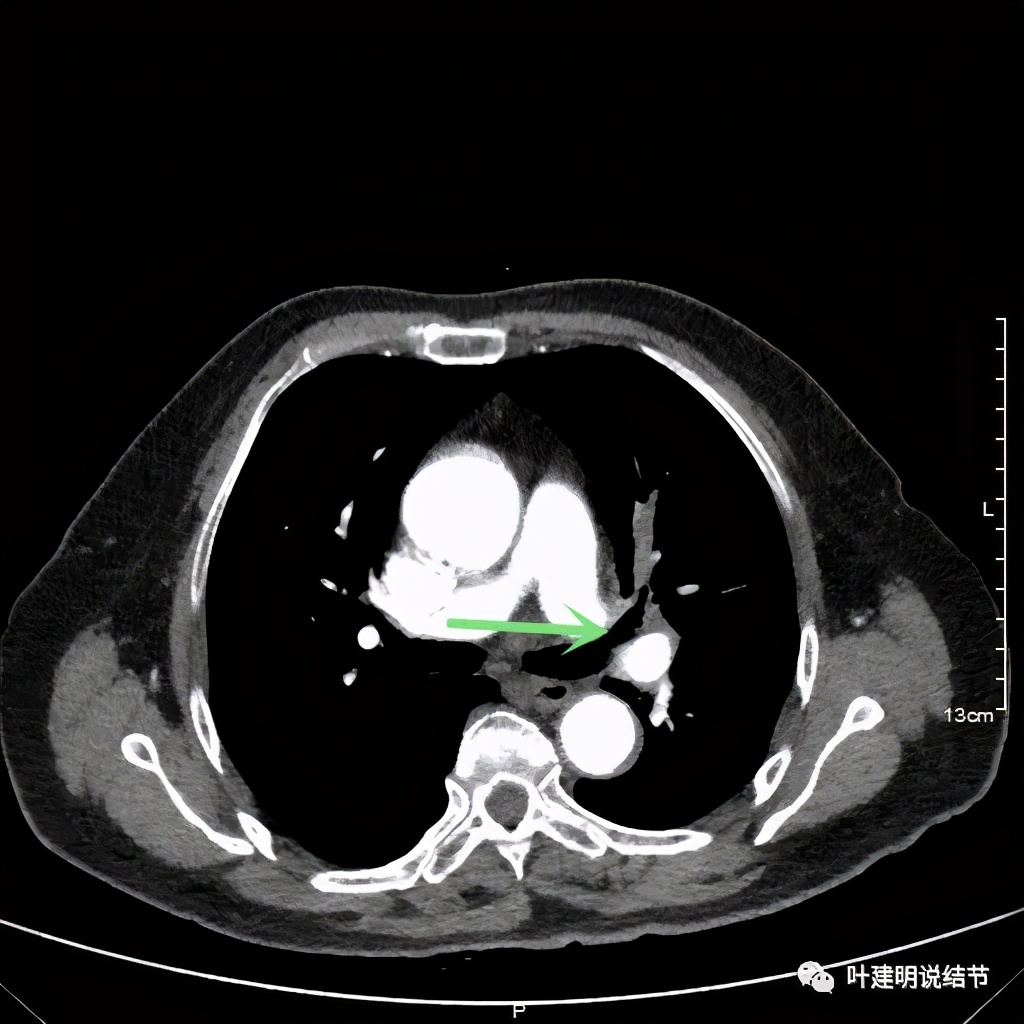

上图示左上叶开口已经显露出来

上图绿色示左上叶支气管,蓝色示下叶支气管开口处